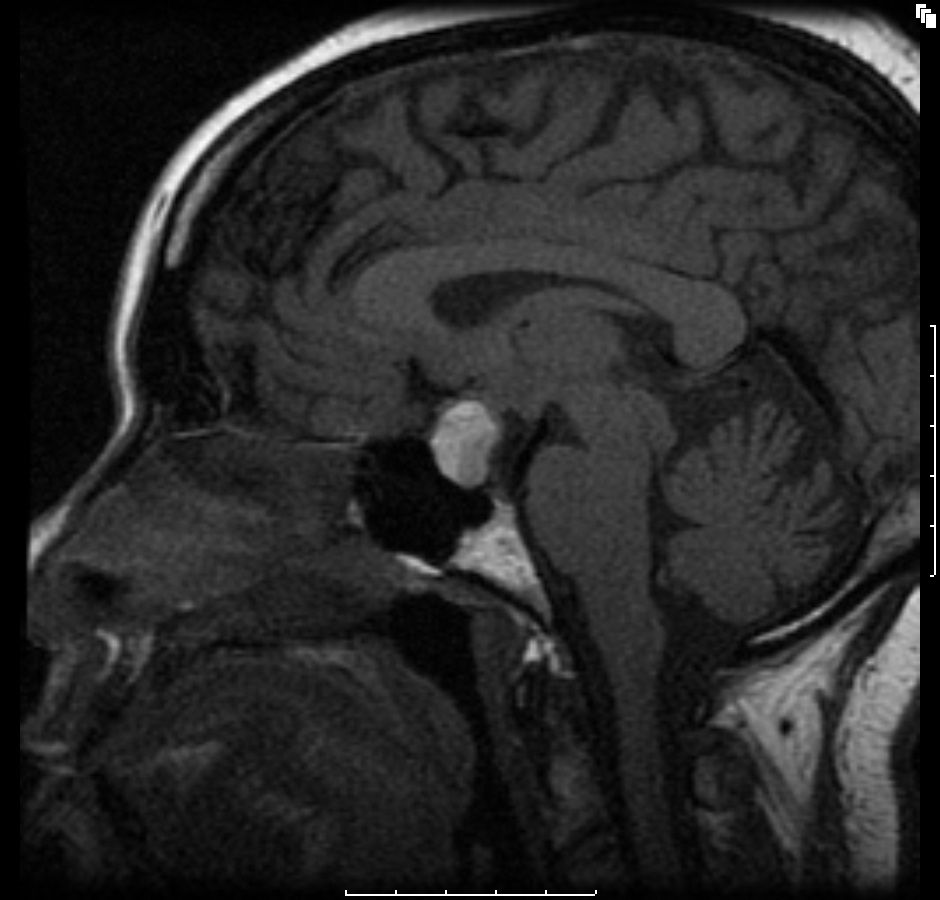

Figure A4: Sagittal T1-weighted image showing a macroadenoma in the sella extending superiorly (blue arrow), with an area of relatively low signal intensity in the posterior pituitary.

The initial brain scans were obtained 6 months after her initial diagnosis (3 months into her pregnancy) and revealed a hemorrhagic pituitary macroadenoma (Figures A1-4). The patient recollects that a week before the scan, she suffered an episode of severe headache with visual disturbance of the right eye. She did not seek medical attention at the time but did keep an appointment for the brain imaging the following week. At the time of the imaging, she reported that her symptoms had fully resolved.

She remained asymptomatic at her clinic follow-up 2 weeks after the episode, and there were no objective focal neurologic deficits. Full ophthalmologic assessment was unremarkable, with no visual field defects. She remained asymptomatic without neurologic deficits and, so far, has no features of hypopituitarism. Repeated scans performed 6 months into the patient’s pregnancy (Figures B1-4; cuts are equivalent to A series) did not show any significant interval changes. She gave birth at 9 months uneventfully and is being followed up regularly for signs and symptoms of hypopituitarism.